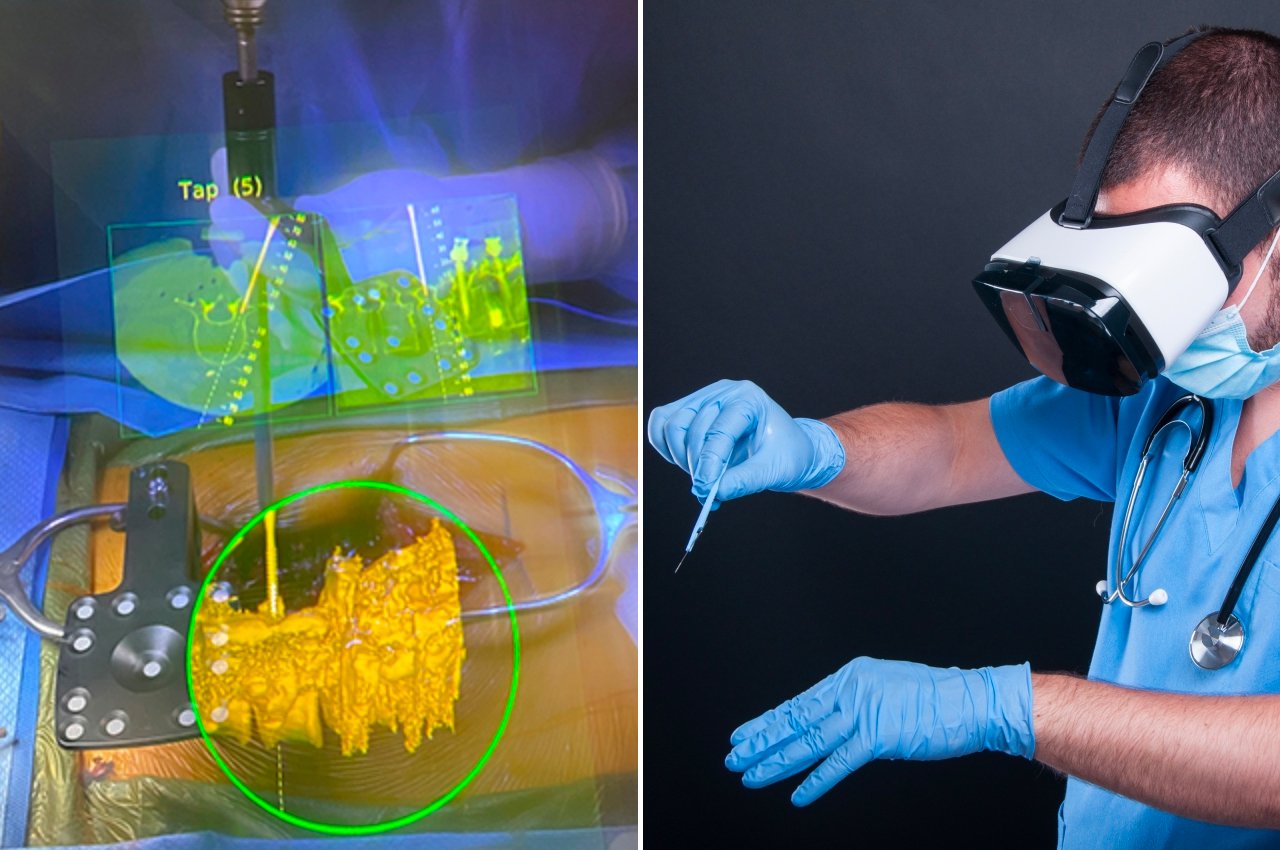

Chirurgia AR

Grazie a Hollywood, molte persone probabilmente immaginano che la chirurgia nel mondo dell'AR e del Metaverso coinvolga medici che eseguono procedure a miglia o addirittura paesi di distanza dal paziente. Anche se ciò potrebbe avere vantaggi salvavita, non abbiamo ancora bisogno di andare così lontano per raccogliere i vantaggi della tecnologia in sala operatoria. Essere semplicemente in grado di vedere più informazioni di quelle che abbiamo fisicamente di fronte fa molto per migliorare la nostra conoscenza e comprensione, che è davvero il cuore della realtà aumentata, senza clamore e sensazionalismo.

I medici richiedono molta immaginazione quando lavorano sui pazienti e non nel modo in cui voli di fantasia. Potrebbero non avere una visione chiara di ciò su cui stanno operando o devono lavorare con materiali microscopici che sarebbero impossibili da vedere ad occhio nudo. Sebbene questi professionisti lavorino in questo modo da decenni, ciò non significa che le cose debbano rimanere così, soprattutto se la tecnologia può aiutare ad alleggerire il carico.

Gli interventi chirurgici assistiti da AR sono già stati eseguiti con molto successo, ma spesso non si sente parlare di quelli in contrasto con le notizie su questa o quella nuova piattaforma Metaverse. Essere in grado di vedere dove perforare un osso o dove mettere una vite può rendere le procedure più rapide e sicure. Ovviamente, avrai bisogno di occhiali AR migliori per farlo accadere perché gli attuali modelli di consumo che abbiamo semplicemente non lo taglieranno sul tavolo operatorio, gioco di parole.

Progettista: Augmedics (via Medicina John Hopkins )